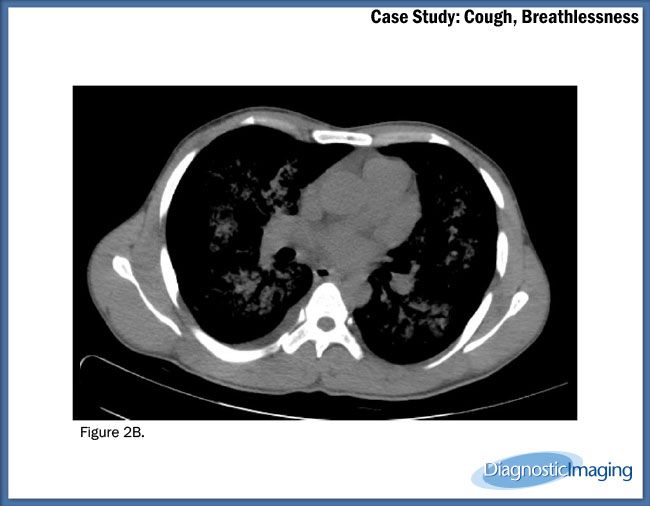

Case History: 22-year-old patient presents with cough and breathlessness.